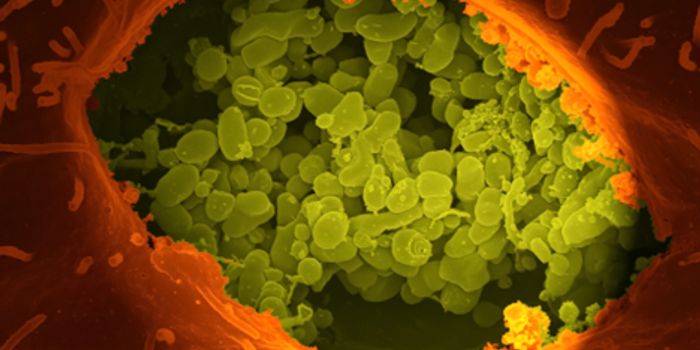

MAY 02, 2024CancerWe interact with small, single-cell organisms on a regular basis. These tiny cells, known as bacteria, represent a ...